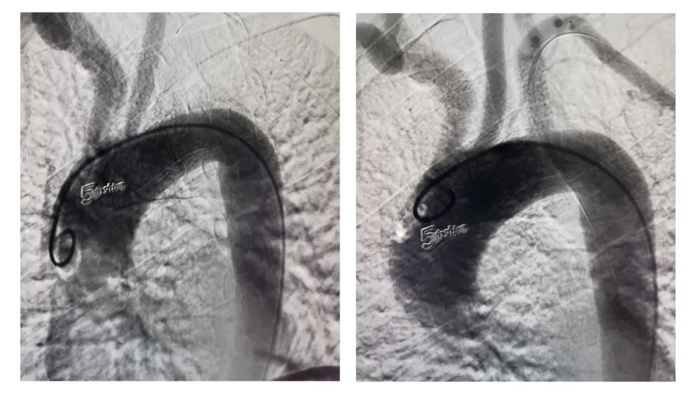

術(shù)前、術(shù)后造影對比圖

在血管外科徐存東主任的指導(dǎo)下,李強(qiáng)主治醫(yī)師作為術(shù)者參與此次手術(shù)的開展。術(shù)中造影證實(shí),鎖骨下動脈起始段完全閉塞,長度>2cm,屬復(fù)雜病變。在嘗試順行開通無果后,果斷穿刺肱動脈,采用逆行入路開通。因?qū)е卵荛]塞的斑塊質(zhì)硬鈣化,在反復(fù)不氣餒地嘗試后,終于將導(dǎo)絲通過閉塞段,隨后對位精準(zhǔn)釋放支架。再次造影可見支架與血管壁貼合良好,前向血流通暢,左側(cè)椎動脈血流正向(TICI分級3級)。歷經(jīng)兩個半小時,手術(shù)順利完成。患者術(shù)后隨即感覺左上肢知覺恢復(fù),麻木感減輕,頭暈癥狀緩解。術(shù)后兩天治愈出院。